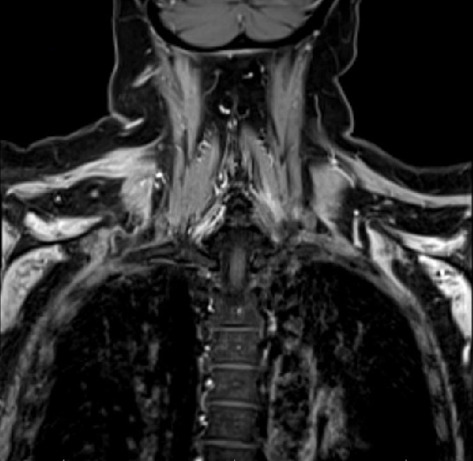

简介:帕森纳-特纳综合征(PTS),也被称为特发性臂丛病,是一种不常见的周围神经病变,双侧PTS的表现更为罕见。嗜血球性淋巴组织细胞增多症(HLH)是一种通常被认为是血液学的高炎症性疾病,但在高达70%的病例中可累及神经系统。病例介绍:56岁白人女性,有SLE、类风湿关节炎、干燥病和桥本甲状腺炎病史,无神经系统病史,因孤立性血小板减少症入院治疗,诊断为HLH,后出现双侧上肢疼痛、无力和麻木。磁共振成像(MRI)显示双侧肩部肌肉轻度对称增强,肌电图/神经传导研究(EMG/NCS)显示双侧肩部肌肉主动失神经支配,支持双侧PTS的诊断。患者开始使用甲基强的松龙1000毫克,连续3天,随后长期逐渐减少类固醇治疗,同时进行物理/职业治疗,症状明显改善。结论:对于新发肩或上臂疼痛、虚弱和感觉缺陷的患者,保持高度的PTS怀疑指数是很重要的,即使发现是双侧的。伴随的炎症性疾病、感染和最近的手术/手术应引起对这种疾病的高度怀疑,并使用相关的诊断方法,如MRI臂丛和肌电图/神经电图,应有助于指导诊断,因为这种情况对治疗非常敏感。

Introduction: Parsonage-Turner syndrome (PTS), also known as idiopathic brachial plexopathy, is an uncommon peripheral neuropathy, and the presentation of bilateral PTS is even rarer. Hemophagocytic lymphohistiocytosis (HLH) is a hyperinflammatory disorder that is normally considered hematologic but can involve the nervous system in up to 70% of cases. Case Presentation: A 56-year-old Caucasian female with a history of SLE, rheumatoid arthritis, Sjogren's disease, and Hashimoto's thyroiditis, but no prior neurologic history, was admitted for the management of isolated thrombocytopenia, diagnosed with HLH, and then developed bilateral upper extremity pain, weakness, and numbness. A diagnosis of bilateral PTS was supported by magnetic resonance imaging (MRI) findings of mild symmetric increased enhancement in the bilateral shoulder muscles, and electromyography/nerve conduction study (EMG/NCS) revealed active denervation in the shoulder muscles bilaterally. The patient was started on methylprednisolone 1000 mg for three days, followed by a long steroid taper along with physical/occupational therapy with significant improvement of her symptoms. Conclusion: It is important to maintain a high index of suspicion for PTS in patients with new-onset shoulder or upper arm pain, weakness, and sensory deficits, even if findings are bilateral. Concomitant inflammatory disorders, infection, and recent surgeries/procedures should prompt a high degree of suspicion of this disorder, and the use of relevant diagnostics, such as MRI brachial plexus and EMG/NCS, should help guide diagnosis, as this condition is very responsive to treatment.